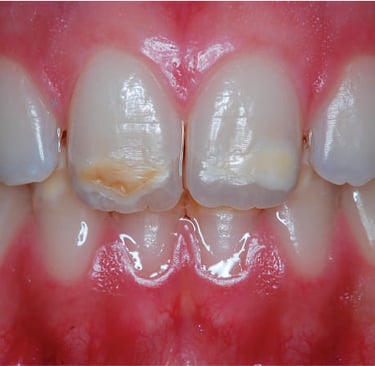

Enamel hypoplasia, characterized by thin, defective, or underdeveloped enamel, poses unique challenges for orthodontic treatment. These patients are more prone to enamel fractures, sensitivity, and an increased risk of caries. Clear aligners, known for their gentler approach compared to traditional braces, can be customized to cater to these patients' needs while minimizing potential risks to their already fragile enamel.

Understanding Enamel Hypoplasia in Orthodontics

Enamel hypoplasia can be congenital or acquired, affecting the structural integrity of the teeth. Key considerations for orthodontic treatment include:

Increased Fragility: Enamel is more prone to wear and fractures during treatment.

Sensitivity: Patients often report heightened sensitivity to thermal, chemical, or mechanical stimuli.

Risk of Decalcification and Caries: The compromised enamel structure makes oral hygiene critical during treatment.